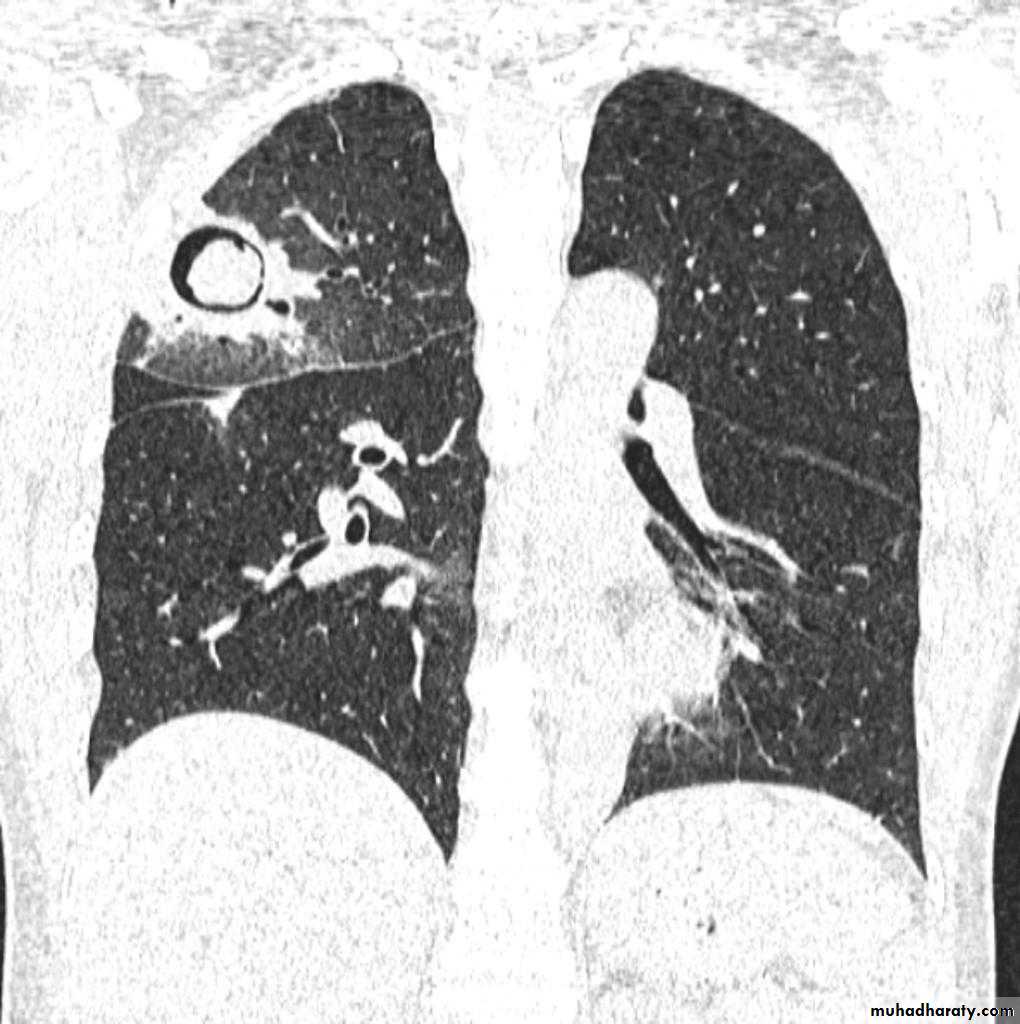

TB abscess

1.patchy consolidation or poorly defined linear and nodular opacities in both apices , upper zone in one lung , & lower zone in other lung ( ulternating lesion ) .2. Post-primary infections are far more likely to cavitate with multiple abscess formation & air fluid level more develop in the posterior segments of the upper lobes.

3. Tuberculomas seen in post-primary TB and appear as a well defined rounded mass typically located in the upper lobes .

Recognized complications include:1.colonisation of cavities by fungus, e.g. aspergilloma